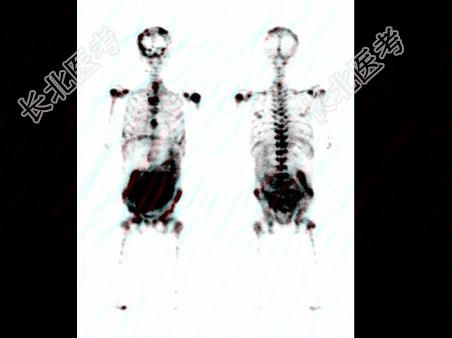

- 多项选择题一患者

Tc

-MDP骨显像如图,的描述是 ( )

A、腹腔浓聚灶很可能是肠道排泄影

B、腹腔浓聚灶可能为软组织钙化

C、广泛骨转移癌

D、腹腔巨大浓聚灶可能为原发恶性肿瘤

E、以上都不是